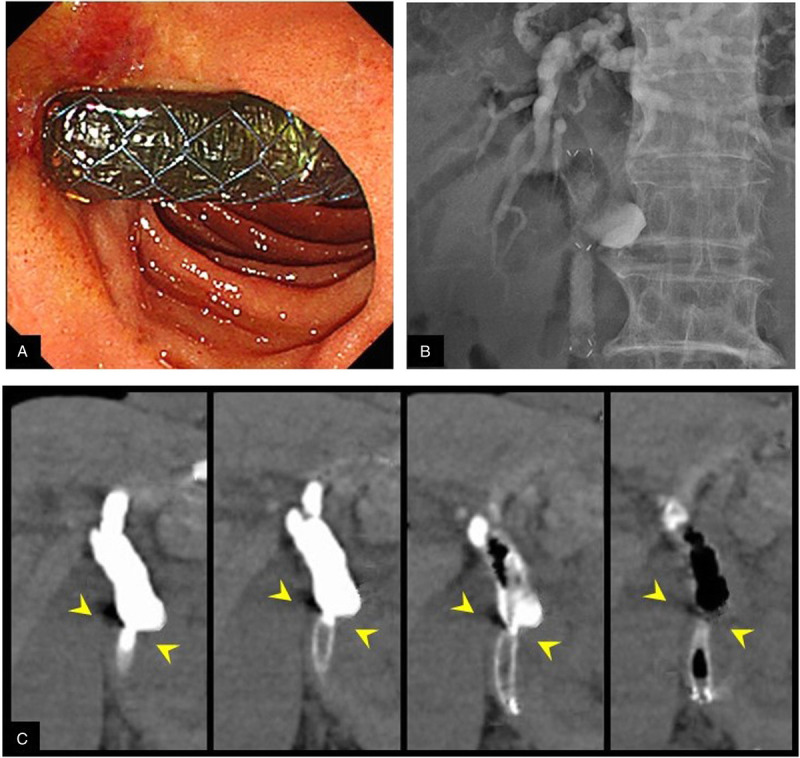

背景和目的:在eus引导下的胆总管十二指肠吻合术(EUS-CDS)中,置入支架前瘘口扩张与不良事件(ae)相关,如胆漏和腹膜炎。我们假设使用一种新型的自膨胀金属支架(SEMS)和薄输送系统无需瘘扩张的EUS-CDS可以克服这一问题,我们进行了这项研究来评估其可行性和安全性。方法:这是一项在单一机构进行的开放标签、单组、II期研究。我们计划使用全覆盖SEMS和5.9 fr输送系统进行EUS-CDS无瘘扩张治疗不可切除的恶性远端胆道梗阻。主要结果是总体技术上的成功。次要结果为技术成功,无瘘管扩张,手术时间,功能成功,复发胆道梗阻时间和ae。计划样本量为25例患者。结果:本研究共纳入24例患者。在21例患者中,EUS-CDS作为主要引流。总技术成功率为100%(24 / 24)。无瘘管扩张的技术成功率为96%(23 / 24)。手术时间中位数为16分钟(范围10-66分钟)。功能成功率为96%(23 / 24)。胆道梗阻复发的中位时间为148天(95%可信区间29-266天)。没有手术相关的不良反应。此外,手术后立即进行的计算机断层扫描显示,没有任何患者的造影剂渗漏到腹腔。结论:eus引导下全覆盖SEMS 5.9 fr输送系统无瘘扩张胆总管十二指肠吻合术是可行的,成功率高,可快速完成,有效预防胆漏和腹膜炎。

Background and objectives: During EUS-guided choledochoduodenostomy (EUS-CDS), fistula dilation before stent insertion is associated with adverse events (AEs), such as bile leakage and peritonitis. We hypothesized that EUS-CDS without fistula dilation using a novel self-expandable metal stent (SEMS) with a thin delivery system could overcome this problem, and we conducted this study to evaluate its feasibility and safety.

Methods: This was an open-label, single-arm, phase II study at a single institution. We planned EUS-CDS without fistula dilation using a fully covered SEMS with a 5.9-Fr delivery system for unresectable malignant distal biliary obstruction. The primary outcome was overall technical success. Secondary outcomes were technical success without fistula dilation, procedure time, functional success, time to recurrent biliary obstruction, and AEs. The planned sample size was 25 patients.

Results: In total, 24 patients were included in this study. In 21 patients, EUS-CDS was performed as primary drainage. The overall technical success rate was 100% (24 of 24 patients). The technical success rate without fistula dilation was 96% (23 of 24). The median procedure time was 16 min (range, 10-66 min). The functional success rate was 96% (23 of 24). The median time to recurrent biliary obstruction was 148 days (95% confidence interval, 29-266 days). There were no procedure-related AEs. Furthermore, computed tomography immediately after the procedure showed no leakage of contrast medium into the abdominal cavity in any patient.

Conclusions: EUS-guided choledochoduodenostomy without fistula dilation using a fully covered SEMS with a 5.9-Fr delivery system is feasible with a high probability and can be achieved quickly while effectively preventing bile leakage and peritonitis.